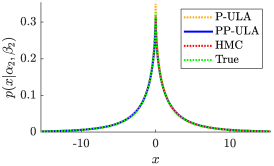

The convergence speed of Algorithm 3 is empirically observed for Simu1 and Simu2, as illustrated in Fig. 2, where we also display the results of the non-preconditioned P-ULA, for which and . Comparing P-ULA and PP-ULA on these simulated data allows us to study the effect of adding a preconditioner in the proposed sampling scheme. As reported in Table II, P-ULA needs more iterations and more time to converge than PP-ULA: the proposed method is 12.2 and 4.8 times faster than P-ULA on Simu1 and Simu2, respectively. In addition, from Table III and Fig. 3, we deduce that P-ULA is more biased than PP-ULA, which samples correctly the target distributions. Finally, as one can see in Fig. 2 and Table IV, P-ULA leads to lower PSNR, SSIM and OA values than PP-ULA. These results clearly emphasize the benefits of preconditioning in this example.

From Table II, PP-ULA is 5.7 and 6.6 times faster than HMC on Simu1 and Simu2 and has better mixing properties, as shown by the MSJ per second. Visual results from Fig. 4 and CNR values in Table IV show that the contrast obtained with PP-ULA is better than with competitors on Simu2, and is second best after P-ULA on Simu1. However, it should be noted that the PSNR and SSIM obtained on Simu1 with P-ULA are much lower than with the other methods. In addition, the PSNR and SSIM values from Table IV obtained with PP-ULA are equivalent or higher than all competitors for these two experiments. Visual segmentation results are shown in Fig. 5, and OA values can be found in Table IV. For these simulated images, more pixels are correctly labeled with PP-ULA than with competitors.